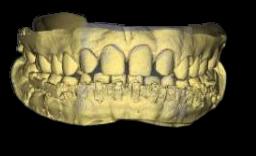

FIGURA 2 (PERIAPICAL PZA. 1.3)

RECONSTRUCCION 3D DE LA ZONA A ESTUDIAR

Las reconstrucciones tridimensionales nos permiten una visualización detallada y precisa de las estructuras vecinas a la pieza retenida, superando las limitaciones 2D de las radiografías convencionales, también ayudara en este caso para la planificación quirúrgica y posterior tratamiento de ortodoncia.

En este caso podemos observar una lesión de diámetro considerable de bordes corticalizados y forma irregular proyectada en el maxilar superior en el cuadrante 1, que se extiende desde distal de la pieza 1.1 hasta distal de la pieza 1.5, desde el tercio apical de las piezas 1.2 – 1.4 y 1.4 por vestibular y desde cervical por palatino. Se evidencia también a la pieza 1.3 retenida desplazada el ápice hacia la cortical palatina y la corona hacia la cortical palatina

CORTES AXIALES

Con la evaluación de la tomografía volumétrica en cortes axiales y transversales se observa la expansión y adelgazamiento de la tabla ósea vestibular y palatina legando a dicha pérdida ósea, también se observa el desplazamiento de la pieza 1 3 la cual se encuentra retenida y desplazada hacia la basal vestibular.

CORTES SAGITALES

A nivel de los cortes sagitales y coronal verificamos la extensión de la lesión y evidenciar el desplazamiento de las piezas 1.2 a mesial y 1.4 hacia distal a causa de la retención de la pieza 1.3 y expansión de la lesión